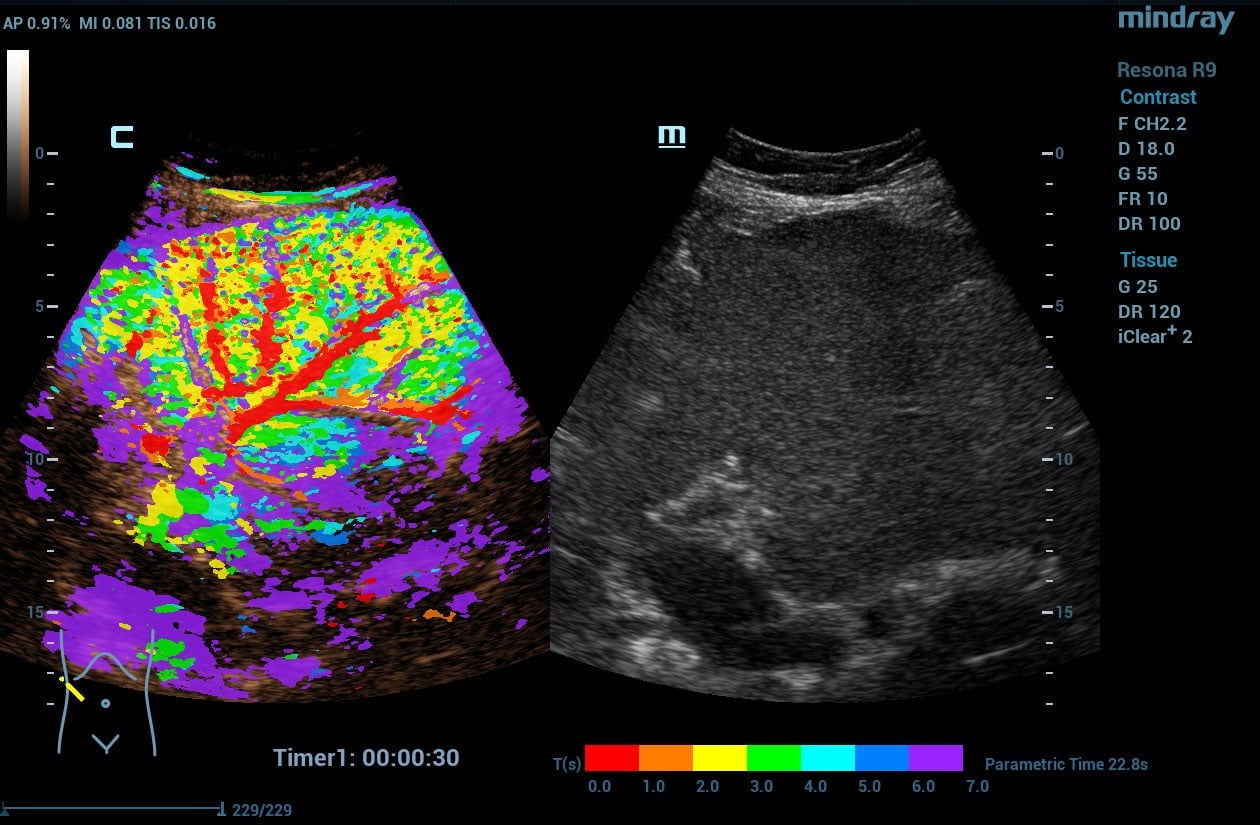

V Flow

V Flow imaging creates a quantitative map of hemodynamic states by tracking the acoustic speckle produced by microstreams of red blood cells as they flow through several non-temporally coherent transmit plane waves. The resulting information is plotted as arrows of varying lengths and colors expressing direction and velocity of blood within the interrogated area.